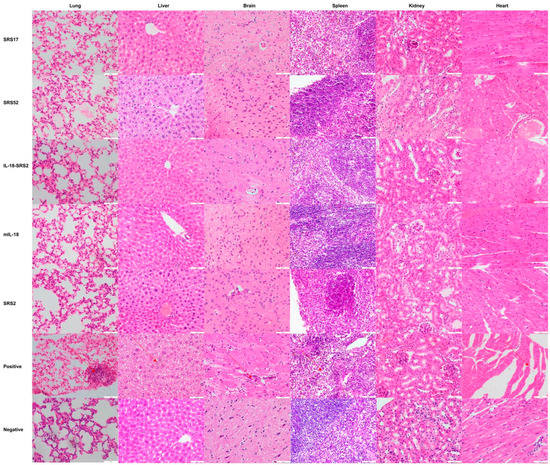

3.2. SRS17 Exerted a Better Protective Effect on Animals after N. caninum Infection

3.3. IL-18 Enhanced the Immunoprotective Effect of SRS2 and SRS17 against N. caninum Infection